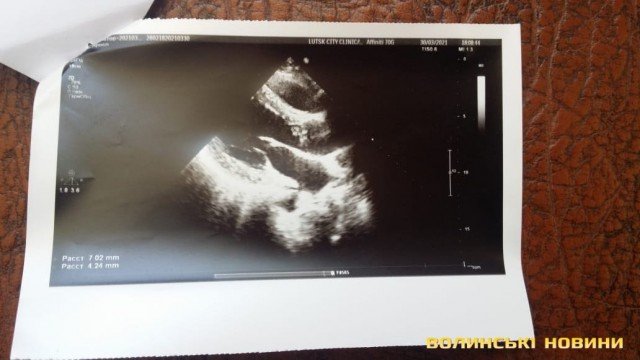

Під час лікування у медзакладі кардіохург поставив атовцю діагноз - первинний інфекційний ендокардит аортального клапана.

Наразі волинянину необхідна операція на серці: треба замінити один із клапанів, що уражений інфекцією, яка може поширитися на здорові тканини. Єдиним правильним рішенням є тільки заміна клапану, інших варіантів лікування, на жаль, немає.